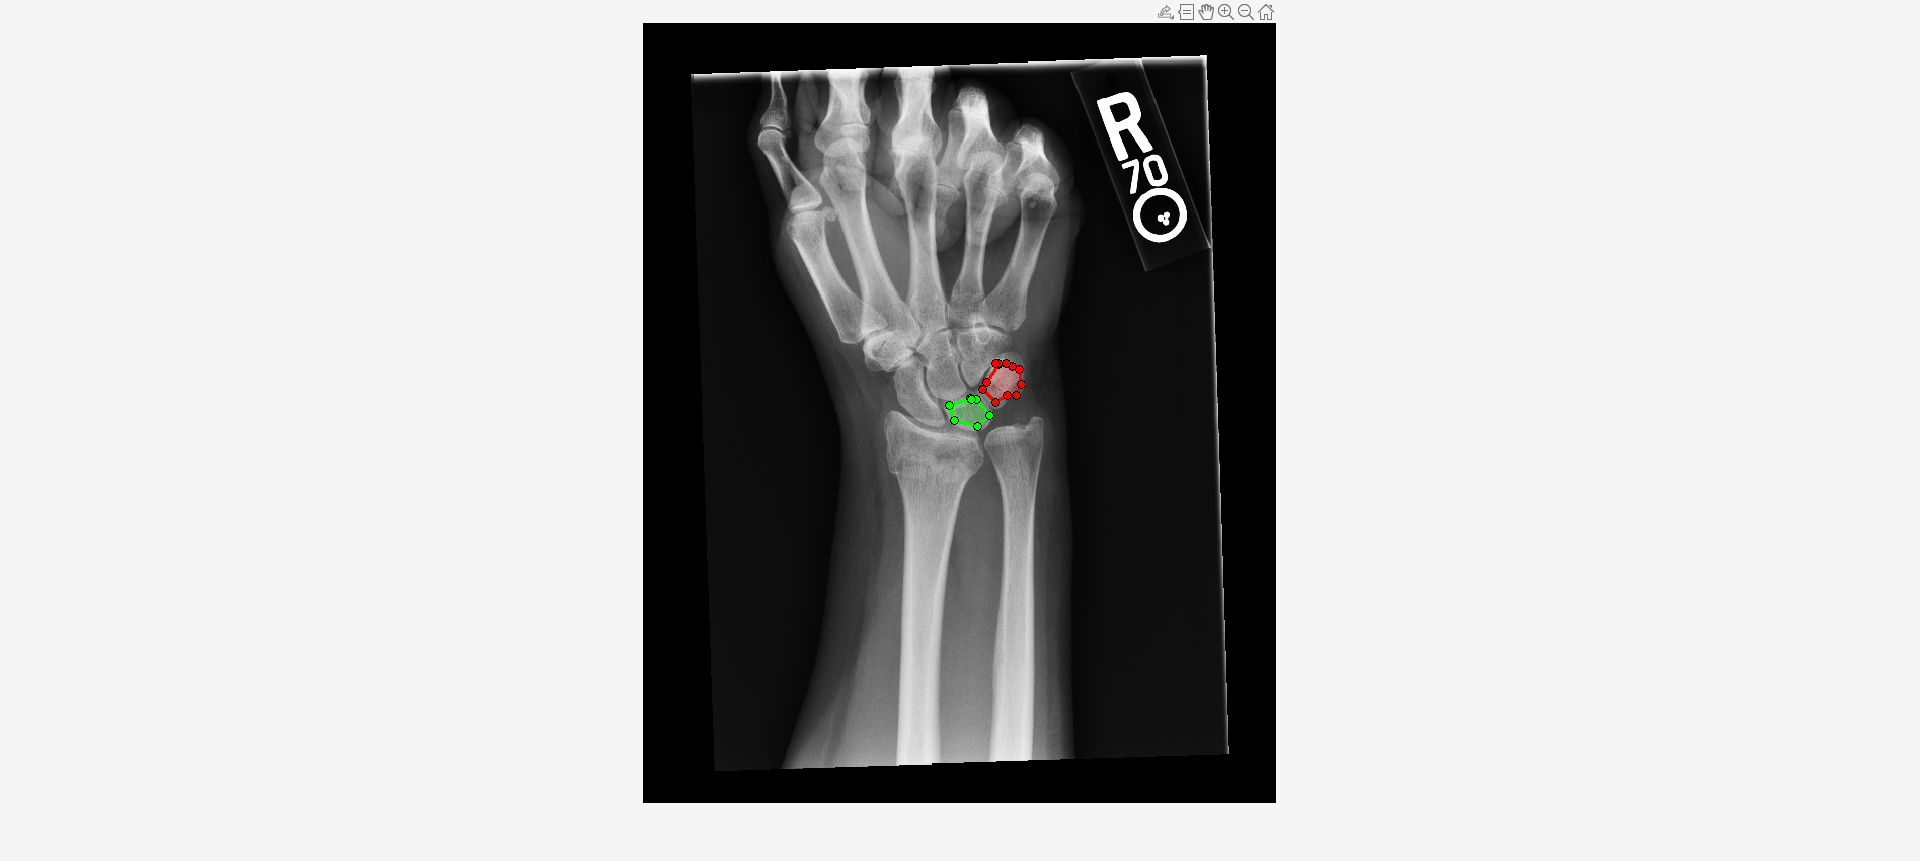

Load an X-ray image into the workspace as a medicalImage object. Visualize the image.

data = medicalImage("forearmXrayImage1.dcm");

I = data.Pixels;

figure

imshow(I,[])Draw two regions of interest (ROI) in the X-ray image. Create masks from the ROIs.

roi1 = drawassisted(Color="g"); roi2 = drawassisted(Color="r");

mask1 = createMask(roi1,I); mask2 = createMask(roi2,I);

Create an ROI label matrix, using different labels for the two ROIs. Create a medicalImage object of the ROI label data.

mask = zeros(size(I));

mask(mask1) = 1;

mask(mask2) = 2;

info = dicominfo("forearmXrayImage1.dcm");

roi = medicalImage(mask,info);Create a radiomics object from the X-ray image data and ROI label data.

Compute shape features for both ROIs.

S = shapeFeatures(R)

S=2×24 table

LabelID VolumeMesh2D VolumeVoxelCount2D SurfaceAreaMesh2D SurfaceVolumeRatio2D Compactness1_2D Compactness2_2D SphericalDisproportion2D Sphericity2D Asphericity2D CentreOfMassShift2D Maximum3dDiameter2D MajorAxisLength2D MinorAxisLength2D LeastAxisLength2D Elongation2D Flatness2D VolumeDensityAABB_2D AreaDensityAABB_2D VolumeDensityAEE_2D AreaDensityAEE_2D VolumeDensityConvexHull2D AreaDensityConvexHull2D IntegratedIntensity2D

_______ ____________ __________________ _________________ ____________________ _______________ _______________ ________________________ ____________ _____________ ___________________ ___________________ _________________ _________________ _________________ ____________ __________ ____________________ __________________ ___________________ _________________ _________________________ _______________________ _____________________

"1" 54 54.427 135.84 2.5156 0.019243 0.13156 1.9662 0.5086 0.96618 0.18567 11.327 10.188 6.924 0 0.67962 0 0.63176 0.65158 NaN 0.91886 0.98182 0.99044 1.2498e+05

"2" 74 74.85 181.6 2.454 0.017061 0.10342 2.1304 0.46939 1.1304 0.24847 11.563 11.187 8.7535 0 0.78246 0 0.64598 0.66783 NaN 0.83862 0.93671 0.9552 1.8045e+05